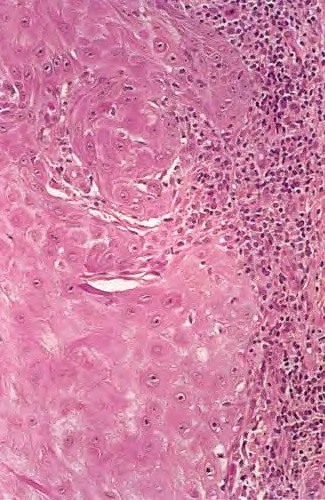

Cytomorphologically, large keratinocytes with eosinophilic cytoplasm are commonly observed, together with atypical cells and mitoses . An inflammatory infiltrate containing lymphocytes, plasma cells, histiocytes, eosinophils, and neutrophils is a common feature, and in some instances may be conspicuous. Neurotropism and even vascular invasion can be observed in otherwise typical keratoacanthomas, but the prognosis does not seem to be affected by these histopathologically worrisome features .